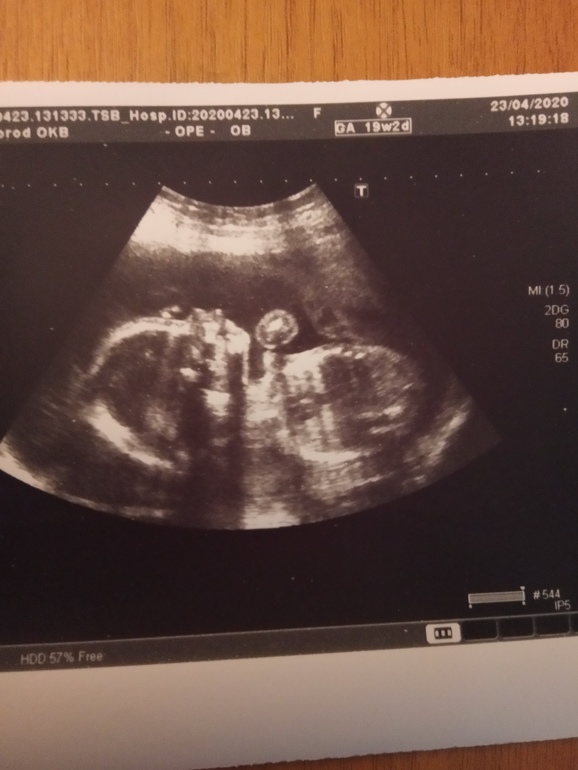

2 скрининг и... МАЛЬЧИК

Пол малышаЯ месяц ждала этого дня и вот он настал. Врач назначил дату УЗИ ещё месяц назад, как же я ждала этот день. Все вокруг пугали что с ребёнком может быть что-то не так, я конечно сильно не принимала такие слова, но волнение появилось. А ещё мне очень хотелось узнать что у меня мальчик...лежу врач водит датчиком какие-то цифры озвучивает и тут он поворачивает монитор ко мне и говорит "мужик" я аж приболдела мой сыночек ножки задрал и всё хозяйство отчётливо было видно 😀 что касается результатов скрининга всё хорошо, малыш развивается и ещё я запомнила вес 381гр